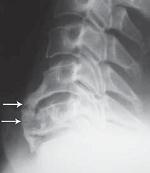

На рентгенограмме № 4 изображен межпозвонковый сегмент в далеко зашедшей стадии дегенерации. Спондилёз второй степени в сочетании со снижением межпозвонкового промежутка говорит о том, что в прошлом на данном уровне имелась протрузия межпозвонкового диска, которая была стабилизирована развившейся стадией фибротизации поражённого диска (что хорошо видно на МРТ № 37).

Бывает, что спондилёз может травмировать эпидуральную клетчатку (при движении позвоночника), в результате чего в ней возникают асептические воспалительные процессы. Эпидуральная клетчатка со временем уплотняется, склерозируется, в ней появляются фиброзные тяжи, которые могут деформировать спинномозговой корешок, вызвать его натяжение или сдавление. А при значительном увеличении (разрастании) спондилёза может развиться стеноз спинномозгового канала второго типа (первый тип стеноза — врождённый, второй — приобретённый), что довольно часто бывает при срыве адаптивных механизмов во время развития дегенеративно-дистрофических процессов в межпозвонковых дисках.